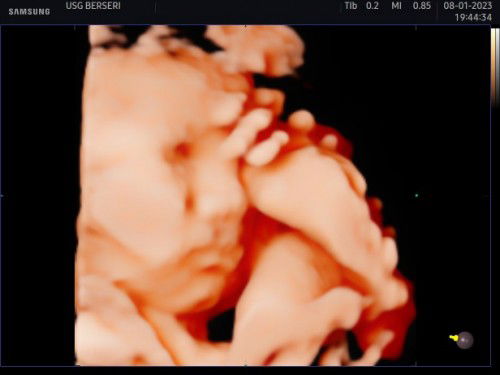

Hasil USG anakku usia 31 Weeks

Halo bun, mau tanya dong disini ada yang suka bingung campur khawatir gitu ga sih sama hasil USG si Dede bayi, aku baru aja USG 4D tgl 8 Januari kemarin, karna dokternya terburu-buru banget jadi agak gak puas sama kontrol USG ku, ngerasa aneh banget bibirnya yang atas kalau dilihat dari hasil usgnya dan ga sempet nanya sama pak dokternya, semoga aja cuma karna si dedenya lagi bete aja ya mom. #seriusnanya #bantusharing #firstmom #firstbaby